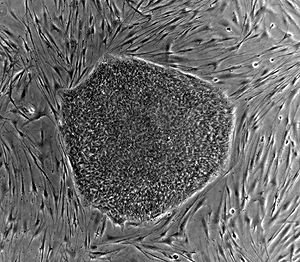

Embryonic stem cell lines (ES cell lines) are cultures of cells derived from the epiblast tissue of the inner cell mass (ICM) of a blastocyst or earlier morula stage embryos. A blastocyst is an early stage embryo—approximately four to five days old in humans and consisting of 50–150 cells. ES cells are pluripotent and give rise during development to all derivatives of the three primary germ layers: ectoderm, endoderm and mesoderm. In other words, they can develop into each of the more than 200 cell types of the adult body when given sufficient and necessary stimulation for a specific cell type. They do not contribute to the extra-embryonic membranes or the placenta.

Nearly all research to date has taken place using mouse embryonic stem cells (mES) or human embryonic stem cells (hES). Both have the essential stem cell characteristics, yet they require very different environments in order to maintain an undifferentiated state. Mouse ES cells are grown on a layer of gelatin and require the presence of Leukemia Inhibitory Factor (LIF). Human ES cells are grown on a feeder layer of mouse embryonic fibroblasts (MEFs) and require the presence of basic Fibroblast Growth Factor (bFGF or FGF-2). Without optimal culture conditions or genetic manipulation, embryonic stem cells will rapidly differentiate.

A human embryonic stem cell is also defined by the presence of several transcription factors and cell surface proteins. The transcription factors Oct-4, Nanog, and SOX2 form the core regulatory network that ensures the suppression of genes that lead to differentiation and the maintenance of pluripotency. The cell surface antigens most commonly used to identify hES cells are the glycolipids SSEA3 and SSEA4 and the keratan sulfate antigens Tra-1-60 and Tra-1-81. The molecular definition of a stem cell includes many more proteins and continues to be a topic of research.